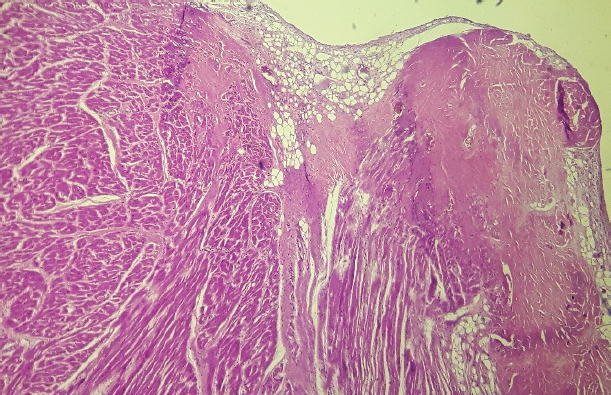

After 24 Holter monitoring, the patient died suddenly during physical activity. Permission for conducting necropsy was obtained from the animal owners. Postmortem examination showed marked cardiomegaly (heart weight bigger than 13 g/kg body weight). No lung edema, pleural effusion or ascites were observed. The heart was explanted and preserved in 10% formalin and then sent for examination to the pathology service of the Hospital Santojani (Buenos Aires), where fragments from both ventricles and the septum were processed with the routine technique to make paraffin-embedded blocks. 4 μm thick sections were cut and stained with hematoxylin-eosin (H&E). Adipose and fibroadipose replacement of the right ventricle free wall of up to 50% of its thickness was observed. These lesions had a predominantly subepicardial distribution. Subepicardial fibroadipose replacement of the left ventricle with involvement of the septum was also observed (Fig. 3). In addition, adipose tissue was also observed in the left ventricle, affecting the base of implantation of the papillary muscles at the septum (Fig. 4). In areas of the left ventricle, co-existence of perivascular fibrosis, myocardial fibrosis suggestive of previous necrosis, and interstitial fibrosis were detected (Fig. 5). In addition, wavy fibers in the myocardium in both ventricles were observed. Clusters of myocardial fibers were also observed within all areas of adipose tissue deposition.

Fig. 5. Free wall of the left ventricle (H&E, 100×). Histopathological image showing connective tissue and adipose tissue deposition, with perivascular fibrosis and interstitial fibrosis.